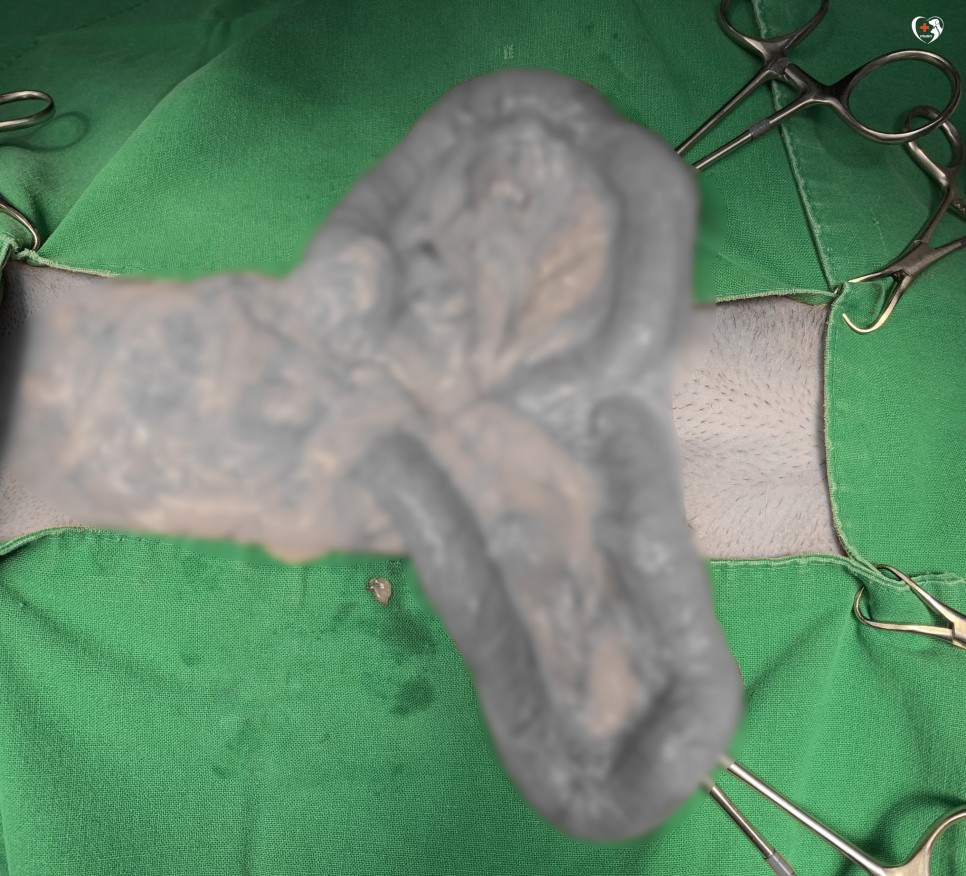

개복을 하고 확장된 자궁을 복강 밖으로 내보내 보았습니다.

위에서 본 복부 초음파처럼 매우 커져 있는 오른쪽 자궁입니다.같은 자궁 축농증으로 24시나 음동물 병원에 내원한 경우와 비교해 볼까요?

왼쪽 사진이 크게 확장된 자궁이었음에도 밍크 자궁이 뚜렷하게 크게 확장되어 있네요?이런 경우 자궁이 갑자기 파열되면 복강 내 오염되어 패혈증, 복막염으로 인해 생명을 잃을 수 있습니다.